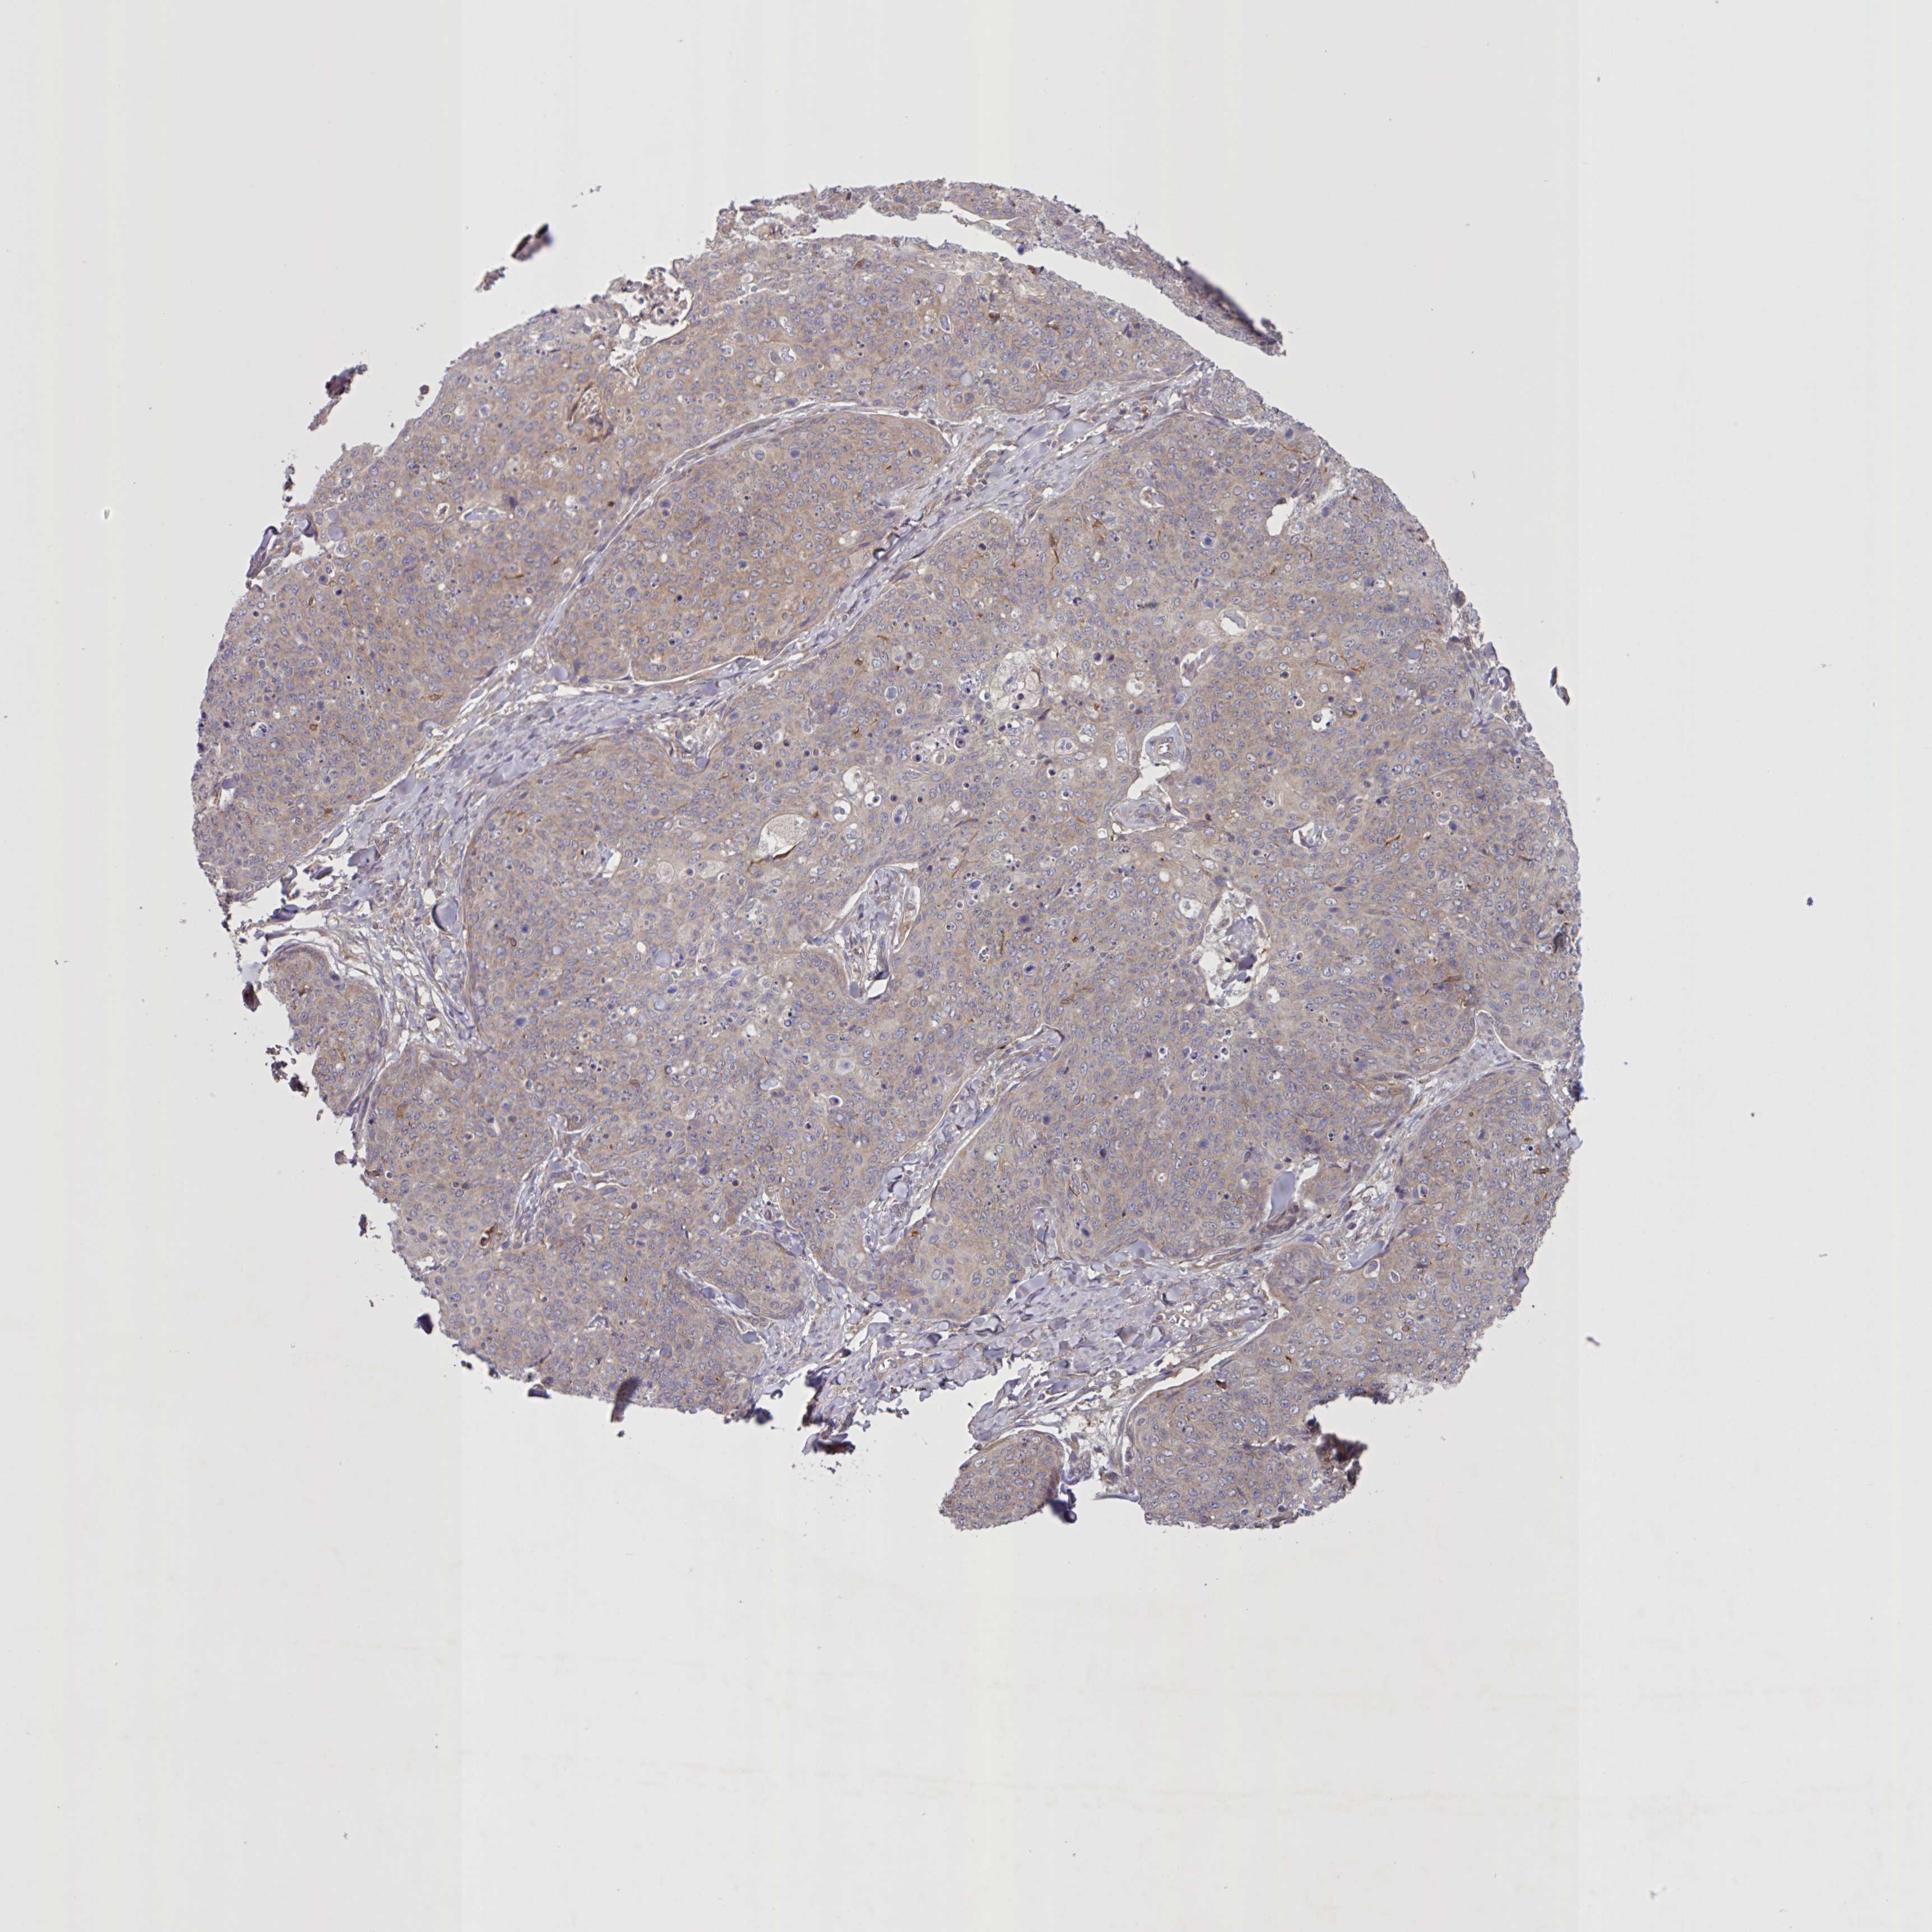

SKIN CANCER - Protein expressioni

A mouse-over function shows sample information and annotation data. Click on an image to view it in a full screen mode. Samples can be filtered based on level of antibody staining by selecting one or several of the following categories: high, medium, low and not detected. The assay and annotation is described here.

Antibody stainingi

Antibody staining in the annotated cell types in the current human tissue is reported as not detected, low, medium, or high, based on conventional immunohistochemistry profiling in selected tissues. This score is based on the combination of the staining intensity and fraction of stained cells.

Each image is clickable and will lead to virtual microscopy that enables deeper exploration of all samples and also displays staining intensity scores, fraction scores and subcellular localization as well as patient and tissue information for each sample.

Antibody HPA052636

Antibody HPA056472

Staining

High

Medium

Low

Not detected

Intensity

Strong

Moderate

Weak

Negative

Quantity

>75%

75%-25%

<25%

None

Location

Nuclear

Cytoplasmic/membranous

Cytoplasmic/membranous,nuclear

Basal cell carcinoma

Squamous cell carcinoma, NOS

Squamous cell carcinoma, metastatic, NOS